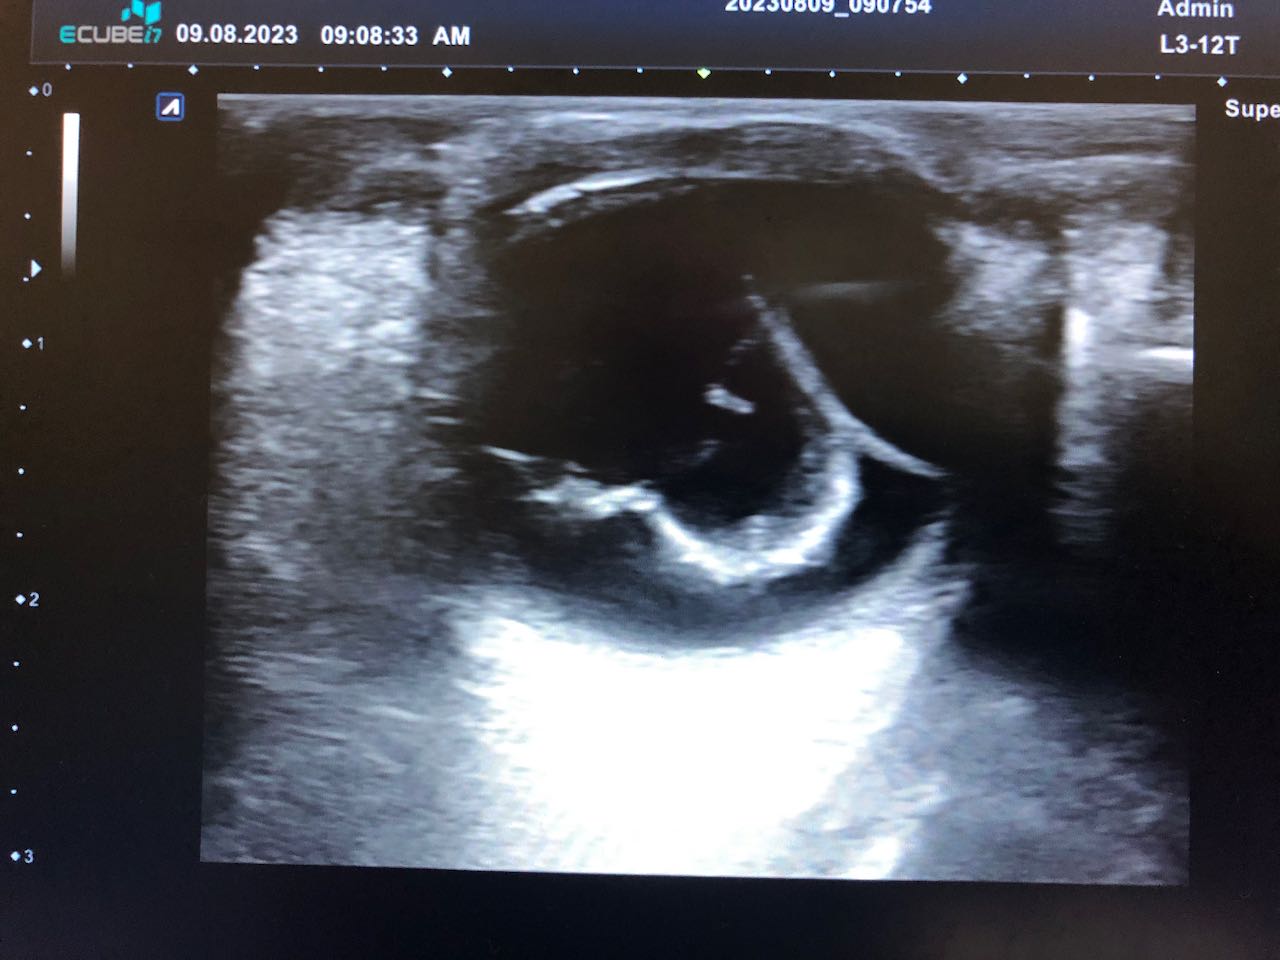

Citado en cita forzada, refiere molestias oculares, con sensibilidad a la luz, que le obliga a mantener el ojo cerrado, acude por precisar gotas para la conjuntivitis, ante la dificultad idiomática y considerar que el paciente es poco preciso en la descripción de los síntomas, pues ante la pregunta de «si tiene dificultades en la visión» el paciente se reitera que le molesta muy cierra el ojo, y en relación con el dolor que es como si tuviera algo que le roza. Se procede a la exploración ocular, observando un ojo derecho normal con blefaroespasmo en ojo izquierdo (OI), hiperemia ocular tarsal, con pupilas reactivas, fluortest negativo y presión intra ocular (medición palpebral), normal en los dos ojos. Ante la incongruencia de la sintomatología referida y los hallazgos exploratorios, se considera indicado hacer una ecografía ocular, en la que se apreció signos de desprendimiento de retina y coroides del OI.

Se confirma desde Oftalmología el diagnóstico: Desprendimiento de retina casi completo junto a desprendimiento de Coroides temporal en OI de contenido hiperecogénico, no se aprecian masas.